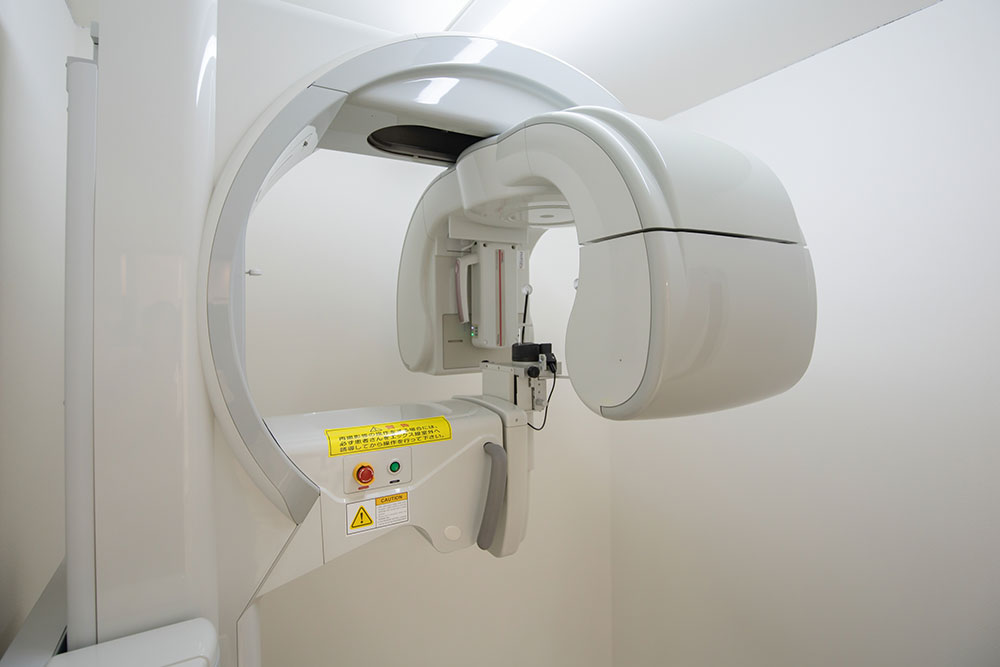

お口の状態の検査

口腔内写真・レントゲン撮影・CT撮影をおこない、現在の状態を精密に確認します。